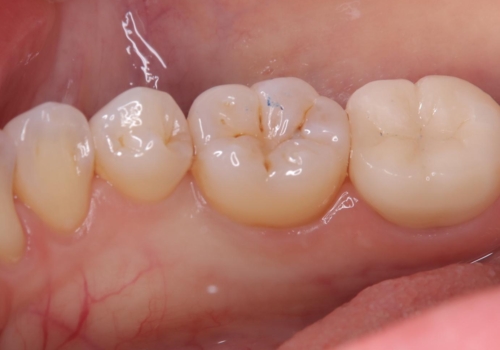

二か月程期間を開け症状が出ていないことと、歯髄診断を再度行い正常反応を確認した後、セラミッククラウン補綴修復を行いました。